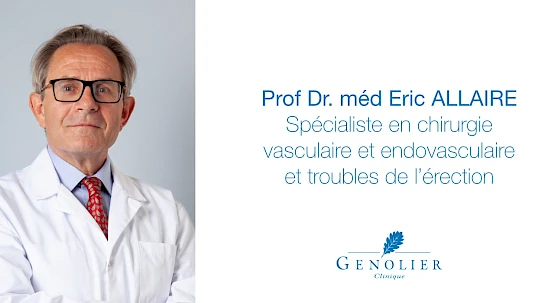

- Clinique de Genolier

- Clinique de Genolier